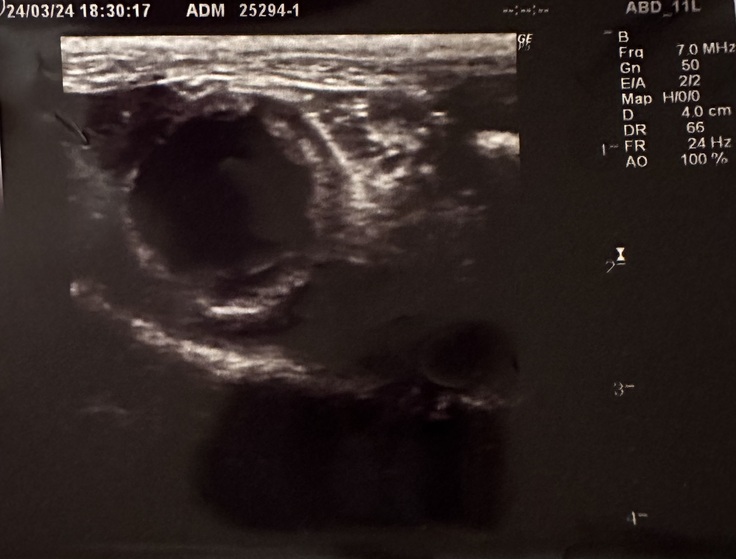

初めは急にご飯沢山食べたからかな...なんて思っていたのですが、念のため執刀医の先生にご相談し、手術先の病院はあまりに遠方であるため、近くの循環器の先生のところへ連れて行き、そこで執刀医の先生と連絡をとりながら色々検査をしていただいたところ胆嚢炎であることが発覚しました。

上の写真は検査初日右が標準の数値。左が検査結果です。

とても数値が高く、胆のうの状態も非常に悪く、危険な状態とお話をされました。心臓がやっと回復へ前進したと思ったら、また命の危機の話をされ...大きな手術、慣れない場所での入院を頑張ってやっと帰ってこれたのに、また病院で...点滴中クレアの鳴き声がなん度も聞こえ、どうして...と何度も思いました。